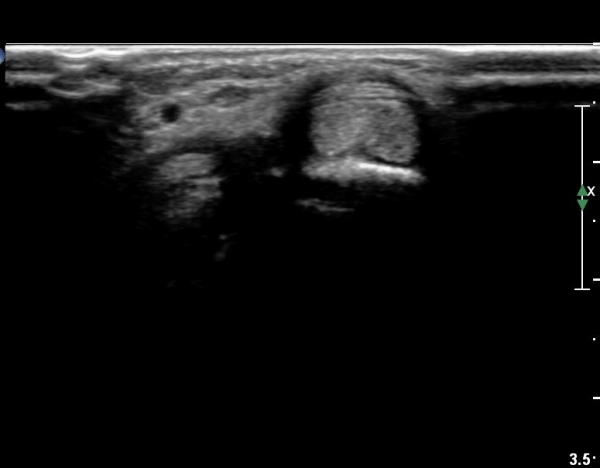

ŽÃËÀÚ¸¦ ¾à°£ ¸»´ÜÀ¸·Î À̵¿ÇÏ´Ï Àå, ´Ü¿äÃø¼ö±Ù½ÅÀü°Ç ºÎÁ¾°ú ÀÌ ½ÅÀü°Ç Ç¥ÃþÀ¸·Î ÁÖÇàÇÏ´Â

À幫Áö½ÅÀü°Ç(EPL)ÀÌ °üÂûµÈ´Ù(»çÁø 4, 5).